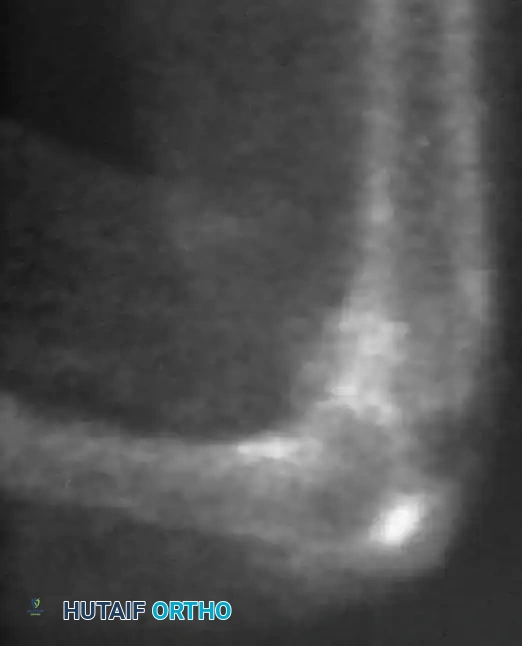

Osteochondritis dissecans (OCD) of the ankle primarily affects the talar dome. The natural history of this lesion in children with open physes is highly favorable compared to adult populations.

Natural History and Imaging

Bauer et al., in a long-term follow-up study (≥ 20 years) of 30 children with ankle osteochondritis, found that only one patient developed severe osteoarthritis. The vast majority experienced complete healing with only minor residual radiographic changes. This is in stark contrast to osteochondritis of the knee, where secondary osteoarthritis is a frequent complication.

Radiographic and MRI evaluation of osteochondral lesions of the talar dome, demonstrating subchondral separation and surrounding edema.